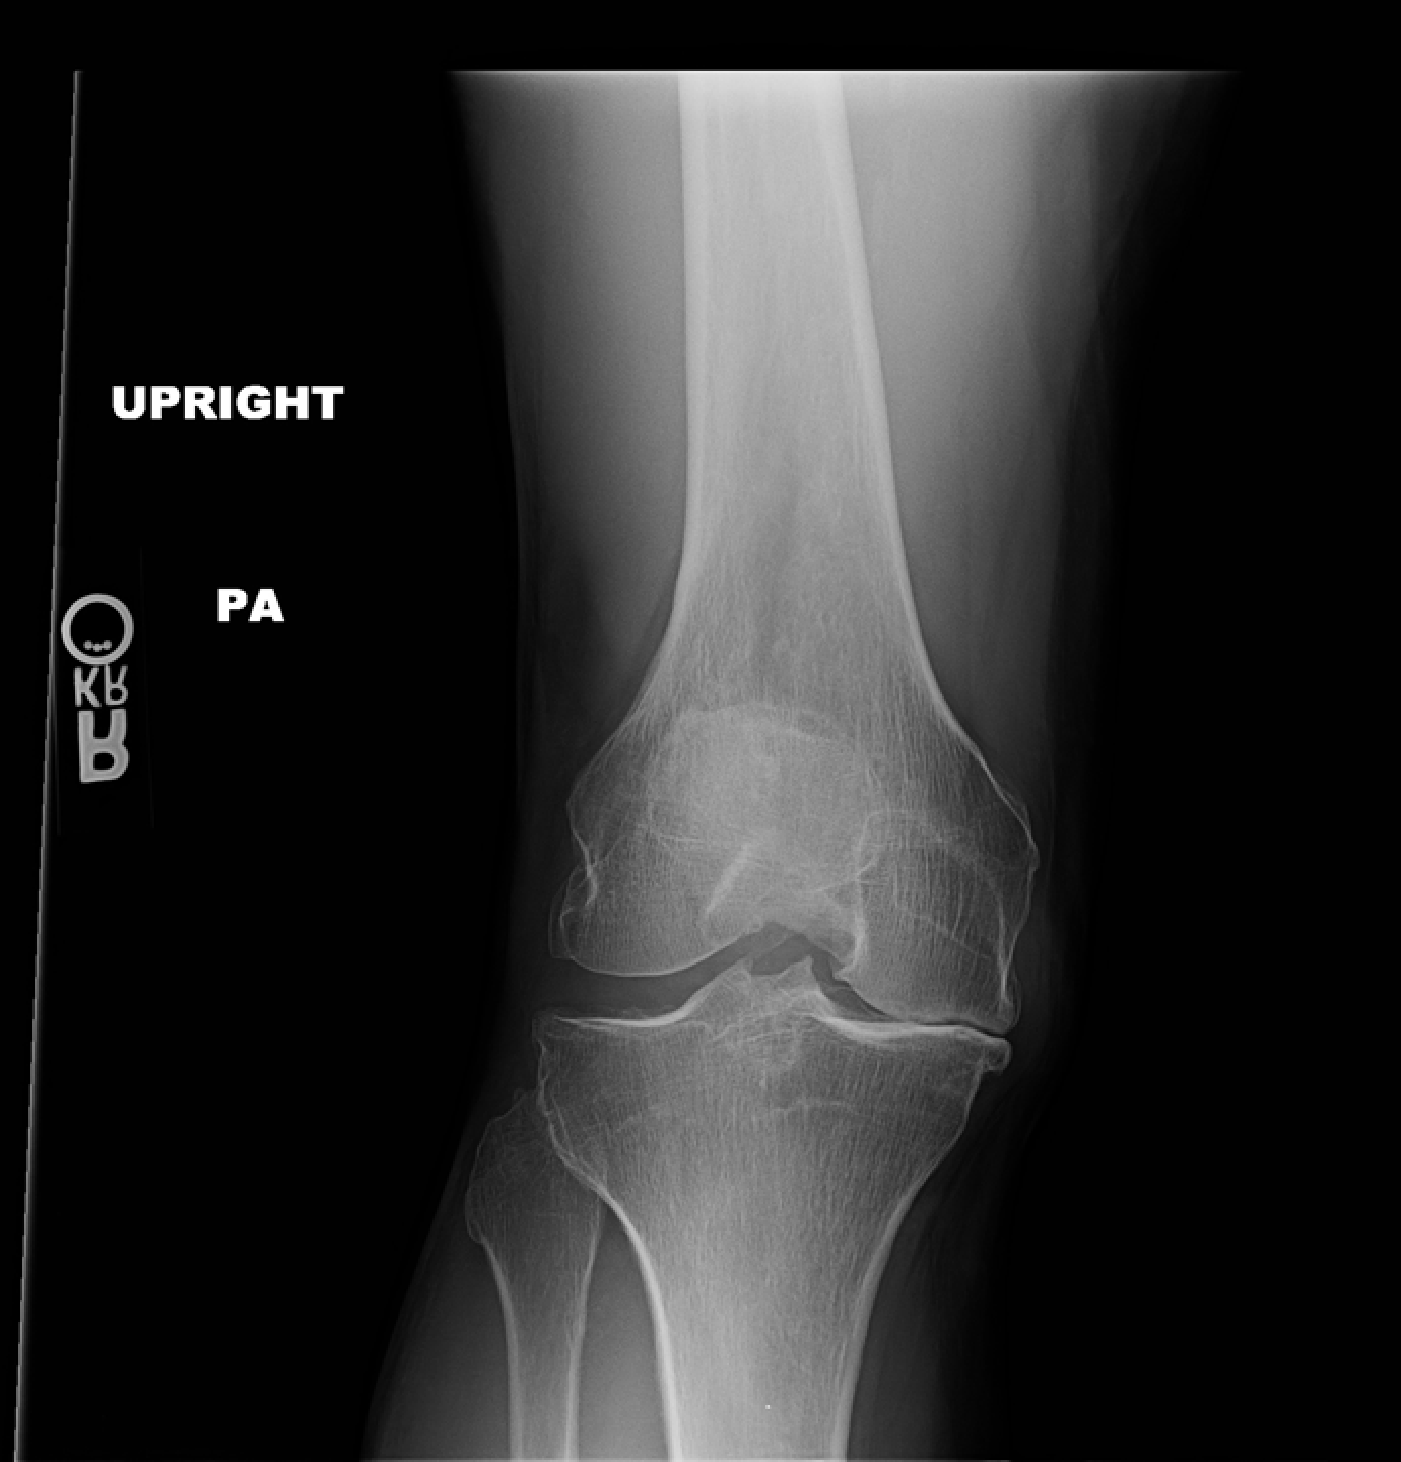

Here is a picture, from the front, of my right knee (Oct 2012). The spacing on the medial side (lookers right) is down to 0.

Compare with the spacing with the artifical knee, in the pics section below.

I sometimes add things to previous links. In the first link of this knee blog I added an Xray of my knee pre-op. It is heartening to compare the spacing in the knee in that Xray to the spacing post-op!